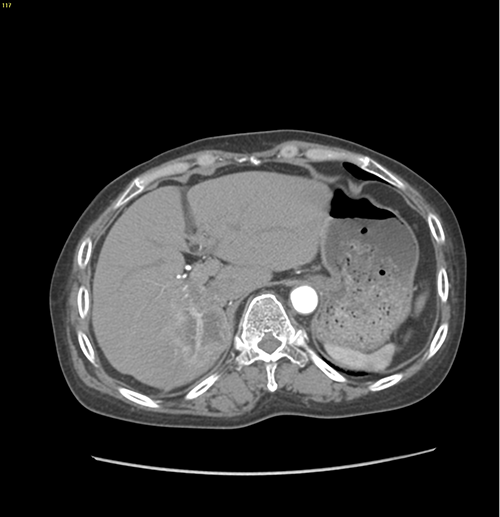

右肝胆管细胞癌-扩大右半肝切除